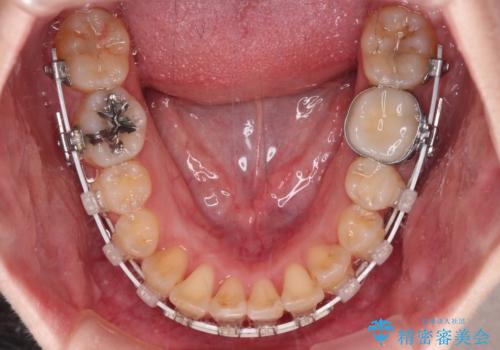

事前にむし歯の疑いがある歯があり、処置を行いましたが、矯正治療中に失活してしまい、ワイヤー装置除去後に、根管治療とセラミッククラウンによる補綴治療を行いました。

矯正治療は2年半ほで無事におけることができました。